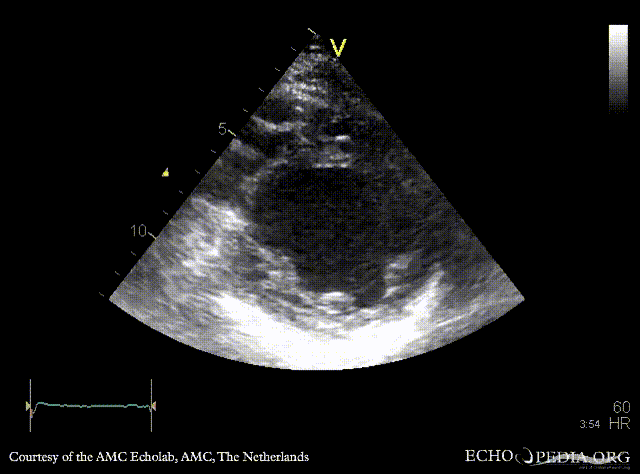

E00705.gif E00706.gif

PLAX: dilated left ventricle, reduced systolic function PSAX